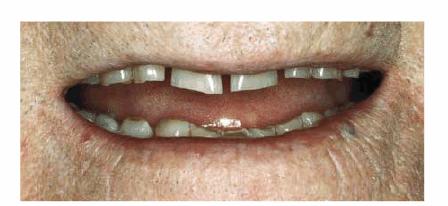

Age and dysfunctional habits can contribute to severe wear over the years. Figures 29-10A, and 29-10B demonstrate evidence of bruxism in an 86-year-old

woman who had been advised to wear a bite guard when she was in her mid 50s.

She disappeared from the practice and returned 30 years later demonstrating

severe wear, loss of vertical dimension, loss of masticatory function, and

temporomandibular pain. More importantly, she was embarrassed by her smile. Her

treatment plan consisted of a temporary crown and bridge to restore vertical

dimension and comfort. She was subsequently treated months later with fixed prosthodontics

using metal-ceramic restorations (Figure 29-10C). She regained much of her self-confidence, as

well as masticatory function, following the esthetic reconstruction of the

maxillary arch (Figure 29-10D) and planned to restore the lower arch.

Figure 29-10A: This lady presented with a severe bruxism habit that resulted in virtually all of her maxillary teeth being hidden when she smiled.

Figure 29-10B: Although she was advised more than 30 years previously to wear a night guard, she chose not to do so.

Figure 29-10C: Crown lengthening followed by prosthodontic reconstruction helped to recreate her smile. The next step is for her to rebuild the mandibular arch.

Figure 29-10D: The reconstructed teeth of this 88-year-old lady now enhance her smile.